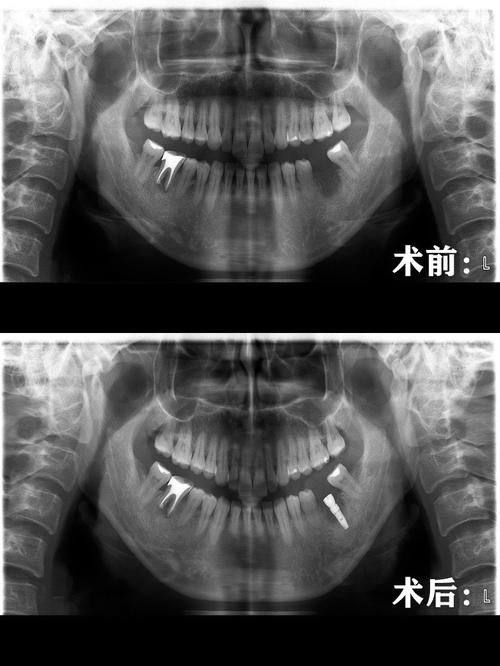

能够熟练运用多种种植牙相关技术,包括穿翼板种植牙技术等,针对牙槽骨吸收重度、骨量不足的患者也可提供适配的种植解决方案。术前依托医院的数字化牙科影像系统精细测算种植位置与角度,保护手术操作的精细性,减少术中创伤,提升术后修复效率。